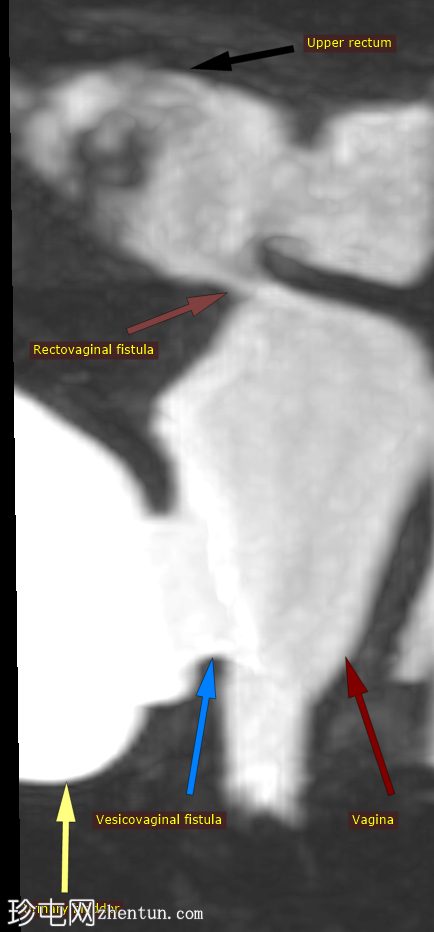

图示

9.png

这张三维重T2加权重建图像在同一张图像中同时显示了膀胱阴道瘘和直肠阴道瘘,从而可以同时观察到两条独立的瘘管。